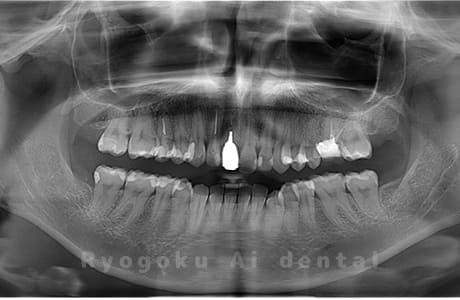

Case24

- 下顎左右の埋伏の親知らず

- インプラント治療は他院でおこなっており、当院で下顎左右の埋伏の親知らずを抜歯したケースです。

<リスク・副作用>

手術後は痛み、腫れ、痺れなどの副作用が生じる場合があります。